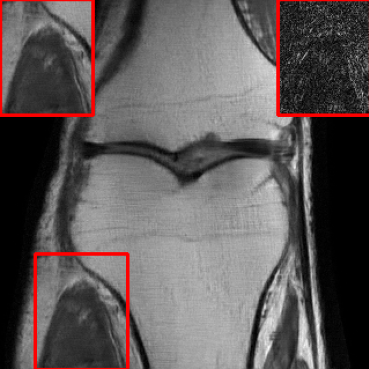

Performance in the Presence of Planted Features: To assess the capability of LONDN-MRI for accurately reproducing image attributes not found in the training set (a common scenario when detecting pathologies, etc.), we embedded artificial features into a knee image from the fastMRI dataset, drawing inspiration from recent work [44]. We performed 4x undersampling in k-space and reconstructed with the MoDL network (with UNet denoiser) that was trained using 3000 images. In Fig. 15, we observe that LONDN-MRI produces sharper reconstruction of image features and better PSNR compared to the globally trained network. The details or edges of the planted features are better preserved in LONDN-MRI. Moreover, LONDN-MRI provides similar image quality with and without the planted features (Fig. 5), whereas, the globally trained network degrades significantly. This indicates the relatively improved stability and generalizability of the proposed method.

Performance on Data with Lesions: While the previous experiment allowed comparing reconstruction quality with or without planted features, here we test our method on MRI scans with lesions, which are often regions of abnormal or diseased tissue. We utilize the annotated fastMRI+ data666https://github.com/microsoft/fastmri-plus/tree/main to evaluate our method’s image reconstruction capabilities, and compare its outcomes with established baselines. For the training phase, the non-lesion dataset was employed for the global training approach with images whereas LONDN-MRI used adaptively selected images for training (searched from images). In contrast, during the testing phase, we used scans with lesions. The results, as displayed in Table V, indicate that our method achieves substantially higher PSNR values in comparison to the globally trained baseline as well as the LORAKI method. Furthermore, visualizations in Figure 16 clearly demonstrate the superiority of our method, particularly in the nonspecific white matter lesion areas. Thus, both in terms of visual assessment and PSNR values, our approach outperforms the existing baselines and aligns more closely with the ground truth.